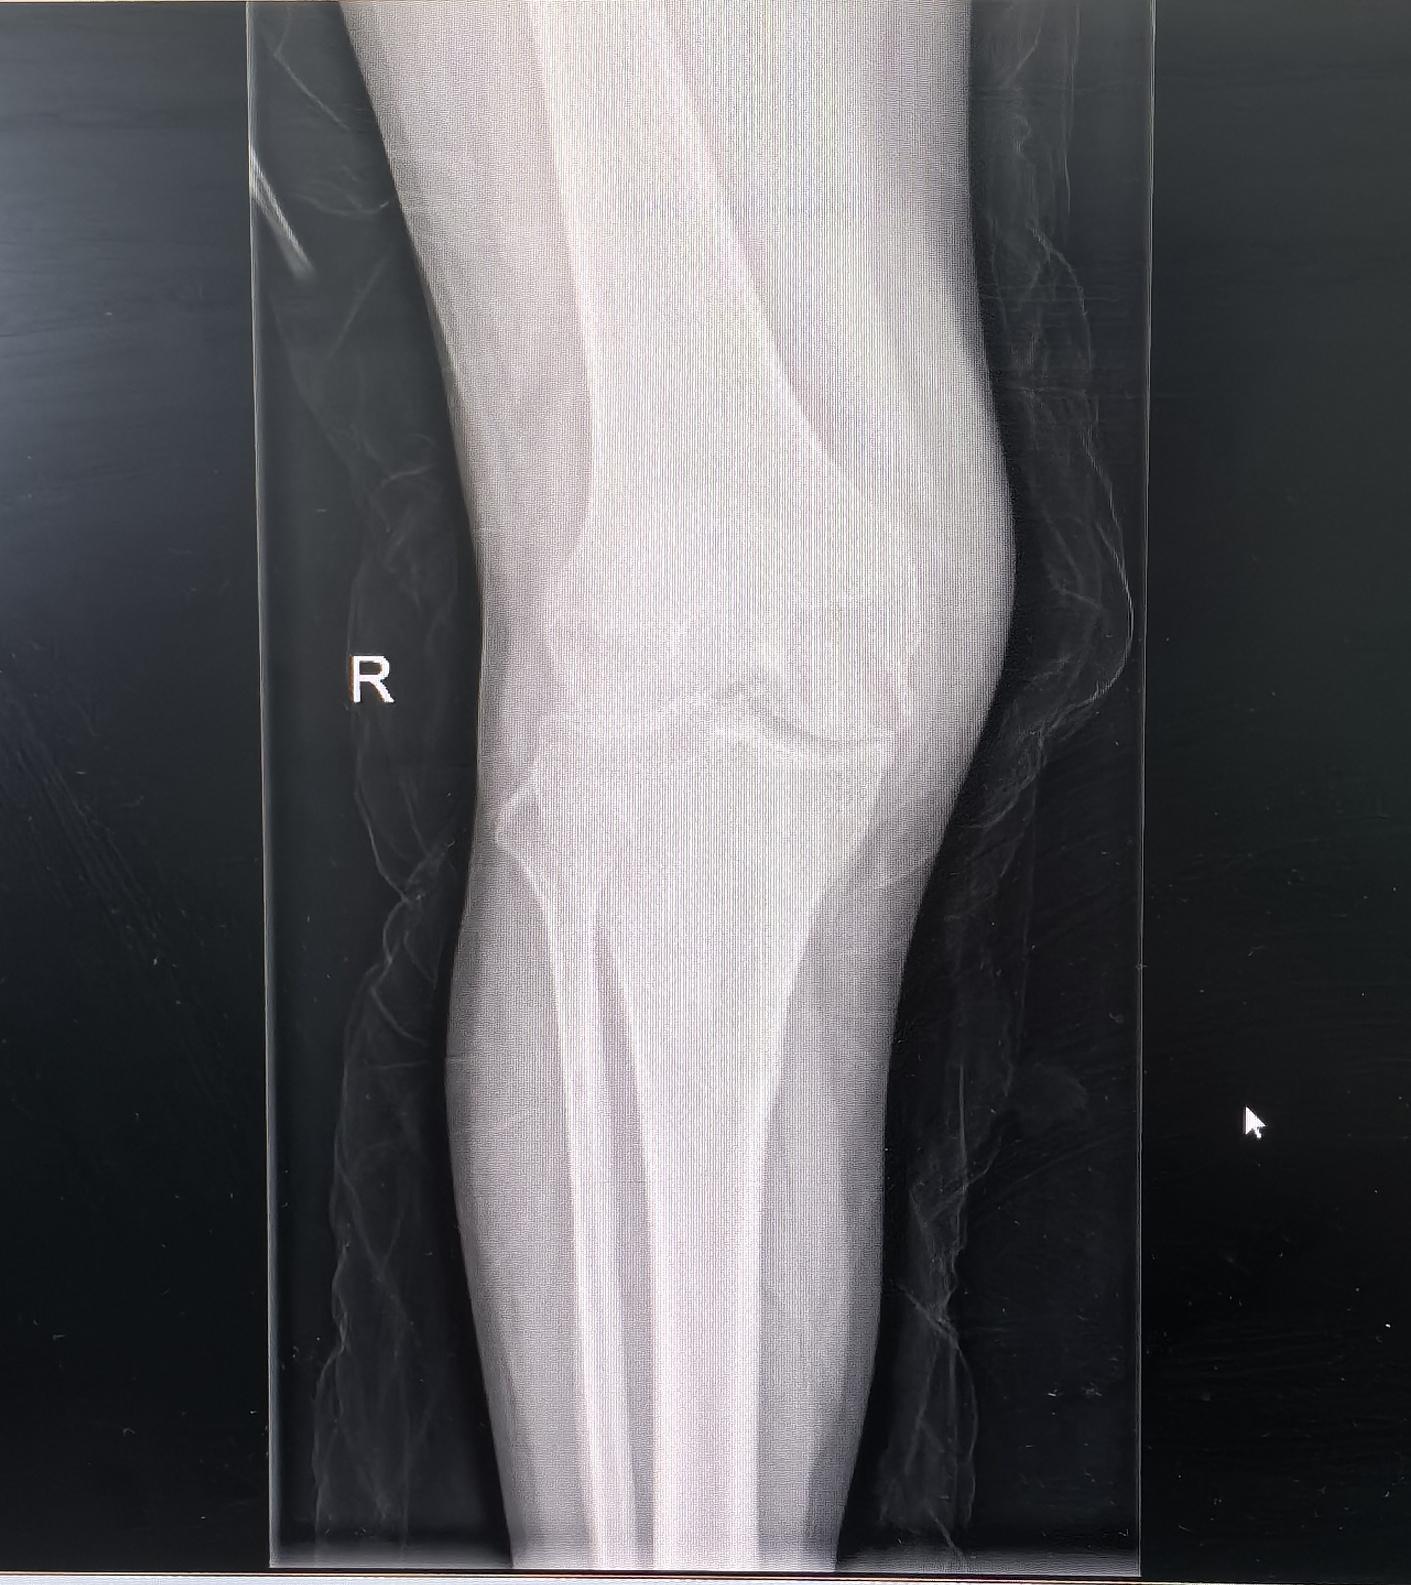

膝关节置换,类风湿关节炎。类风湿关节炎,屈曲挛缩合并外翻畸形